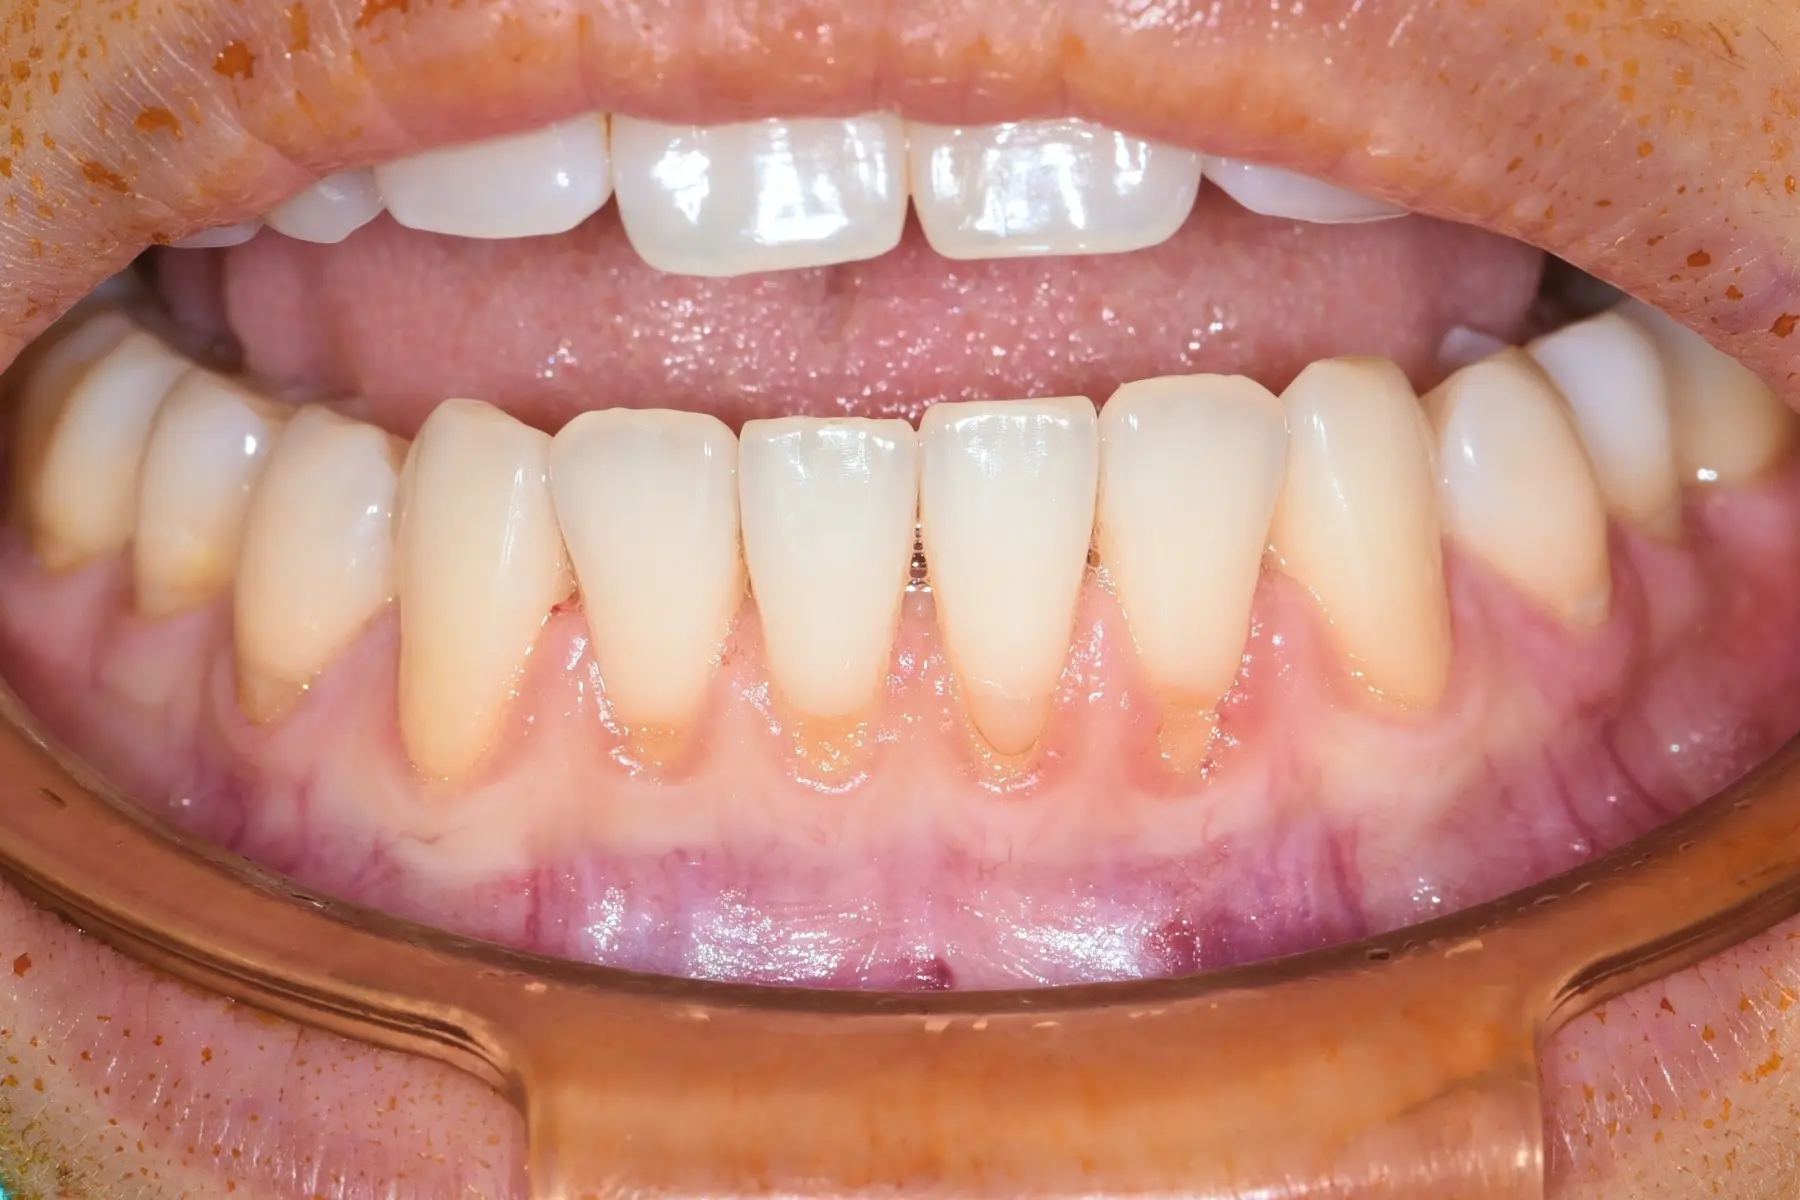

• 術前 18

術後 17

牙根覆蓋術

主治醫師

• 林明志

治療時間

單次療程

主訴

前牙牙齦萎縮露出牙根,想評估牙齦增補手術